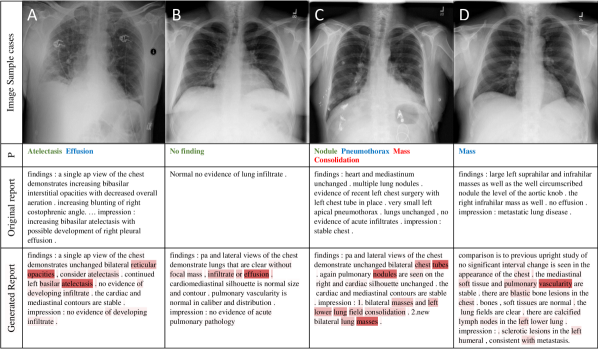

Figure 4: 4 sample image Classification Predictions (P) along with original and generated reports. Text attentions are highlighted over the generated text. Correct predication is marked in green, false prediction in red and missing prediction in blue.

Figure 10 illustrates 4 sample results from the proposed automatic classification and reporting system. Please see more examples in the appendix A. Original images are shown along with the classification predications, original reports and generated reports. Text-attended words are also highlighted over the generated reports. If looking at generated reports alone, we find that they all read well. However, the described diseases may not truly appear in the images. For example, ‘Atelectasis’ is correctly recognized in sample A but ‘Effusion’ is missed. ‘Effusion’ (not too far from the negation word ‘without’) is erroneously highlighted in sample B but the system is still able to correctly classify the image as ‘No finding’. In sample D, the generated report misses ‘Mass’ while it states right about the metastasis in the lung. One promising finding is that the false predictions (‘Mass’ and ‘Consolidation’) in sample C can actually be observed in the image (verified by a radiologist) but somehow did not noted in the original report, which indicates our proposed netowrk can in some extent associate the image appearance with the text description.

In this section, we present 20 more classification and reporting results (case E-X) from the proposed TieNet in addition to the four examples (case A-D) shown in the main paper. Sample images are illustrated along with associated classification Predictions (P), original and generated reports. Text attentions are highlighted with different saturation levels over the generated text. Darker red means higher weights of the text attention. Correct classification predications are marked in green, false predictions in red and missed predictions in blue.